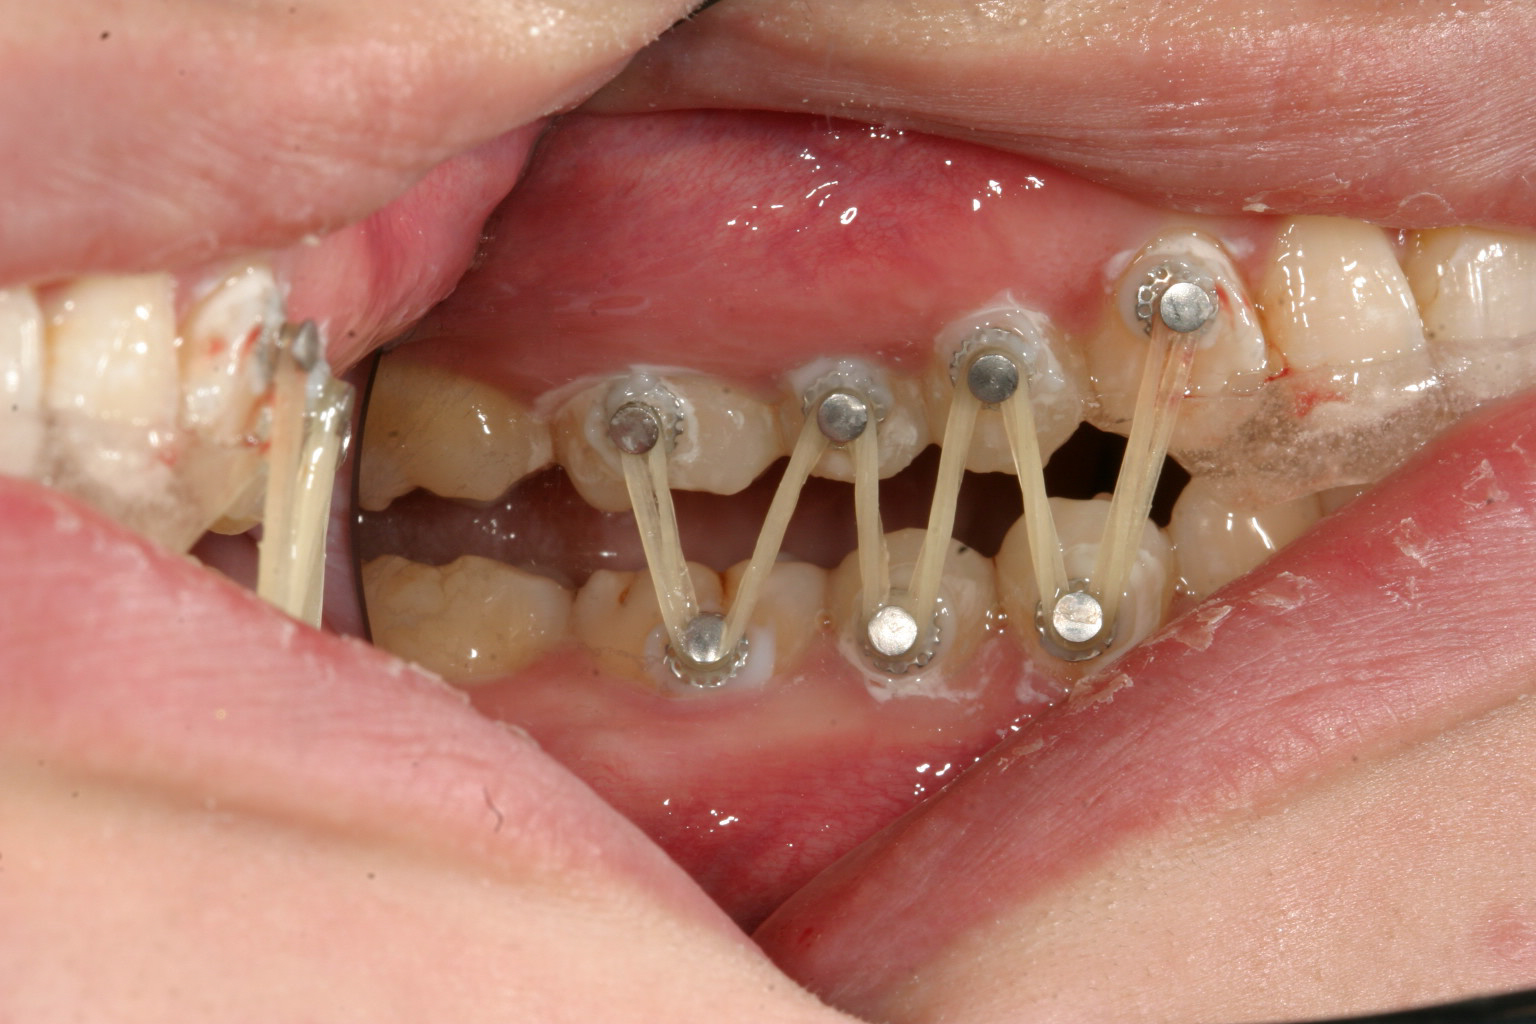

前歯部に自家製のジグ咬ませて左側にアップダウンエラスティックを使用してます。